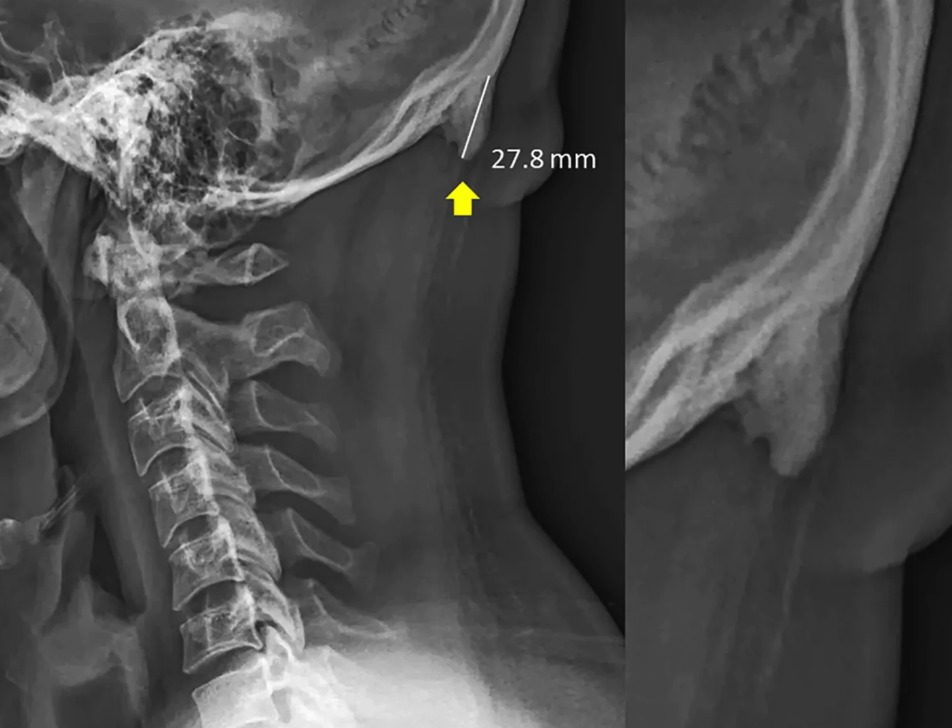

¿Pero por qué? por culpa del uso prolongado del celular. Los jóvenes desarrollan esta especie de cacho o púa en la parte posterior de su cabeza por la inclinación de esta misma hacia adelante. La presión provocada en la espina hacia los músculos en la parte de atrás ha causado un crecimiento del hueso, para ayudar a los tendones y ligamentos.